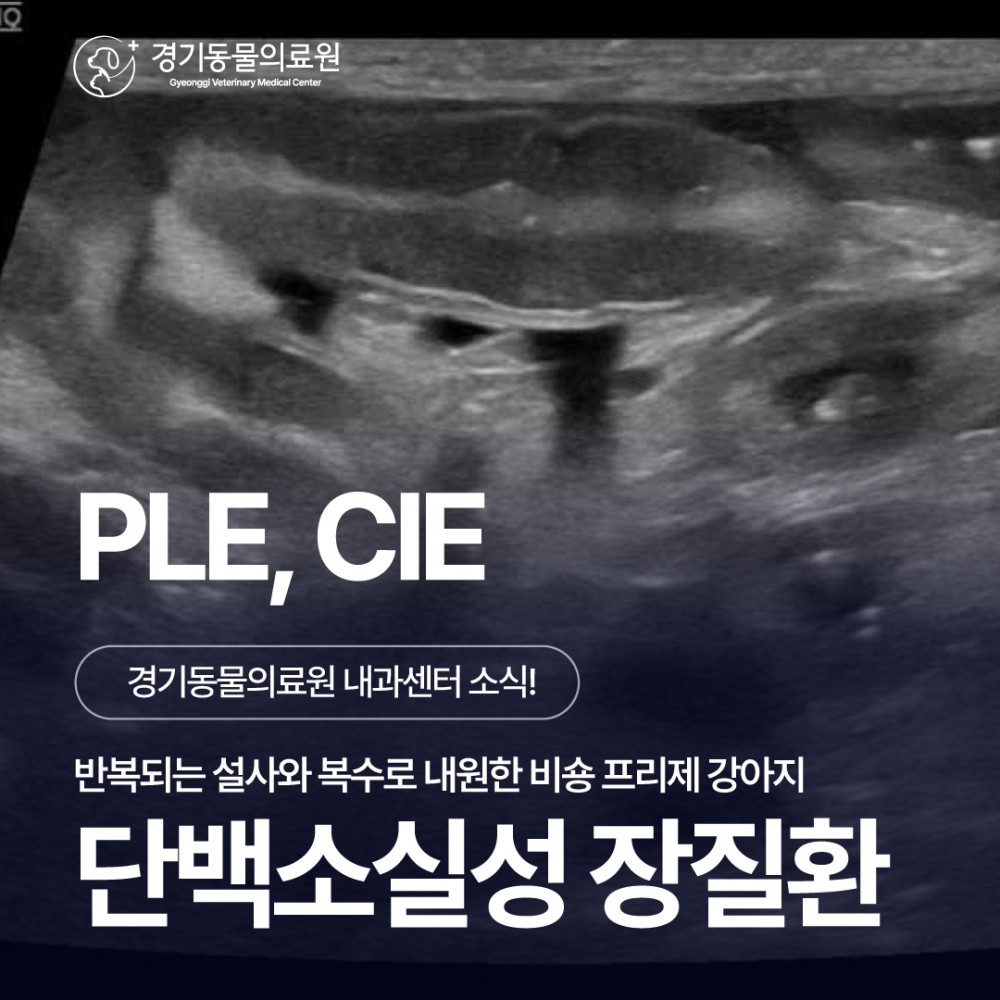

초음파 검사

복부 초음파에서는

- 소장 전반의 점막이 비정상적으로 밝게 보였고,

- 장 점막에 줄무늬 모양의 변화(striation sign)가 반복적으로 관찰되었습니다.

- 장 내에는 액체 저류가 동반되어 있었으며,

- 결장에는 심한 설사 형태의 변이 확인되었습니다.

- 복강 전반에는 중등도의 복수가 존재했고,

- 장 주변 지방 조직에도 염증성 변화가 동반되어 있었습니다.

이러한 소견은 장 점막을 통해 단백질이 지속적으로 소실되고 있는 상태, 즉 단백 소실성 장질환(Protein-losing enteropathy, PLE)을 강하게 시사하는 결과였습니다.

추가로 담낭 내 슬러지와 담낭 및 담도벽의 비후가 확인되었는데, 이는 복수로 인한 부종성 변화와 연관된 소견으로 판단되었습니다.

이상의 검사 결과를 종합하여, 나무는 단백 소실성 장질환(Protein-losing enteropathy, PLE)이 가장 강하게 의심되는 상태로 평가되었습니다.